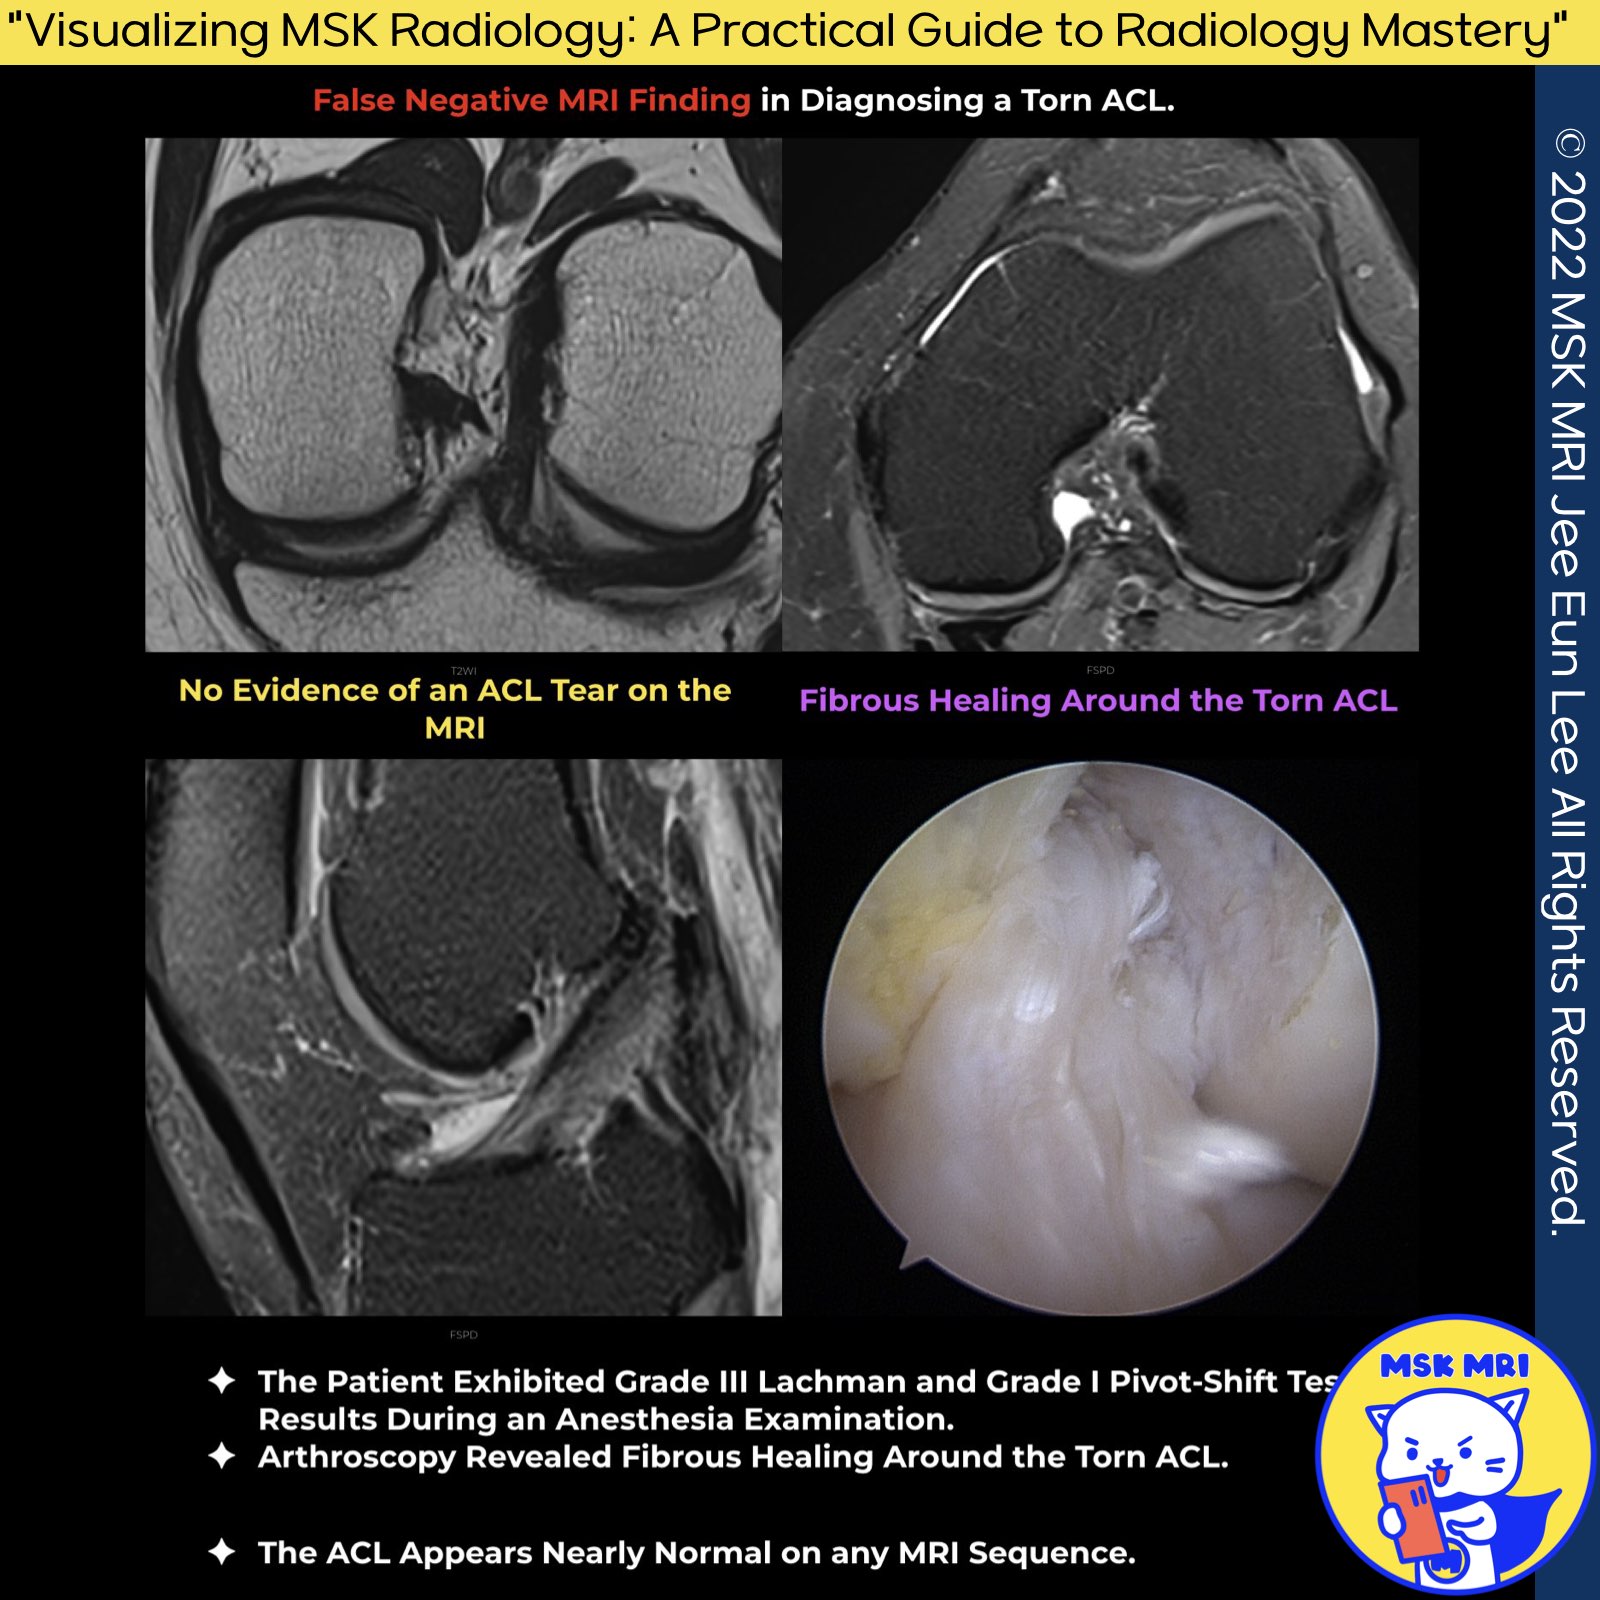

★ Patterns of ACL Scarring:

- End-to-End Scarring: The torn ends of the ACL heal by connecting each other.

- Scarring to the PCL: The ACL forms scar tissue that attaches to the posterior cruciate ligament (PCL).

- Scarring to the Roof of the Intercondylar Notch: The ACL scar tissue attaches to the upper area of the intercondylar notch

- Scarring of the Distal Remnant to the Anatomic Origin: The lower part of the torn ACL attaches back to its original site.

★ General Observations on ACL Scarring:

- The scar tissue from the ACL most frequently attaches to the lateral side of the proximal PCL and the intercondylar notch. It is less common for the scar to attach back to the ACL's original attachment point.

- Among these patterns, scarring that reconnects the ACL to its original attachment point is rare but results in the most significant improvement, leading to reduced laxity (looseness) during clinical examinations.

- Even if the ACL forms a continuous structure through scarring, the healed ligament is usually functionally weaker than before the injury.